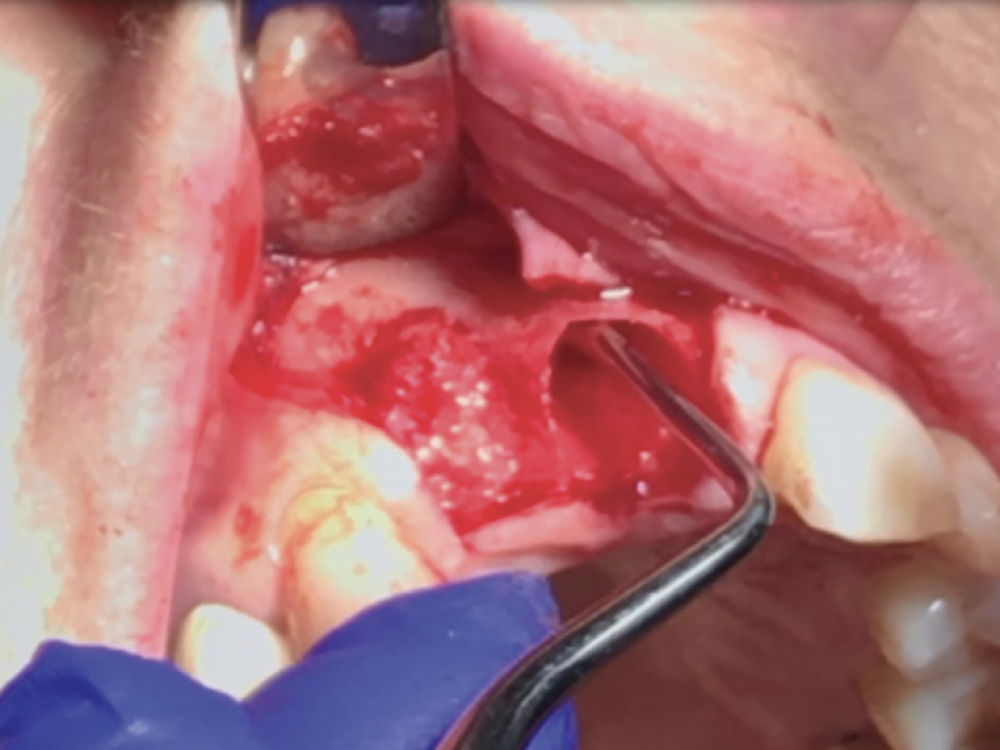

Technique A Severed Periodontal Ligament

Technique B Multi-rooted Tooth

Atraumatic extraction technique: (a) Severing the periodontal ligament fibers, which results in mobilty of the tooth; (b) Multi-rooted teeth should always be sectioned prior to removal to avoid damaging the socket walls.